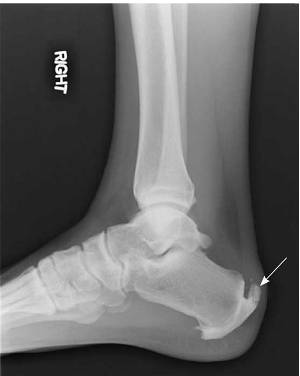

Деформация Хаглунда – костный нарост, который носит название экзостоз, он появляется на задней поверхности пятки несколько выше места, к которому прикрепляется ахиллово сухожилие. Этот нарост со временем начинает увеличиваться в размерах, а это приводит к тому, что он начинает давить на само сухожилие, вызывая воспалительное заболевание, которое носит название тендинит. Также давление оказывается и на ретрокальканеальную сумку, что вызывает другой вид воспаления – бурсит.

Именно эти два компонента – костный нарост и воспалительный процесс играют большую роль в развитии симптомов этой патологии. При слабо выраженном воспалении кожа на пятке имеет нормальный цвет, а под ней без труда прощупывается шишка. Если же есть выраженный воспалительный процесс, то само костное образование будет мягким.